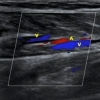

一起聊聊超声检查的那点事